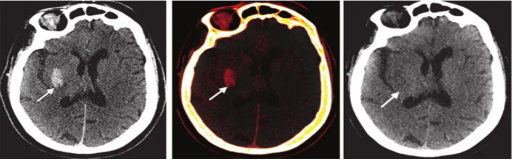

病例二:右侧基底节区造影剂外渗

图片2

(图像:虚拟平扫图高密度灶消失,碘叠加图显示明显碘聚集——证实为单纯对比剂外渗,无出血)